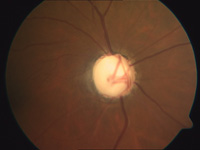

Der Grüne Star ist eine Erkrankung, die der Betroffene lange nicht bemerkt. Ein relativ zu hoher Augendruck beeinträchtigt Durchblutung und Funktion des Sehnervs. Es folgen ein fortschreitender Verlust von Sehnervenfasern mit zunehmenden und charakteristischen Veränderungen des Sehnervenkopfes (Papille) sowie die Verengung des Gesichtsfeldes.

Eine spezielle Tomographie des Sehnerven (HRT III-Untersuchung) gibt schon wesentlich früher Aufschluss darüber, ob möglicherweise ein Glaukomschaden vorliegt. Ab dem 40. Lebensjahr sollten Sie deshalb regelmäßig – mindestens alle zwei Jahre – zum Augenarzt gehen. So kann mit Medikamenten oder gegebenenfalls auch mit einer Operation (Lasertrabekuloplatik) ein Fortschreiten des Glaukoms verhindert und wertvolles Sehvermögen erhalten werden.